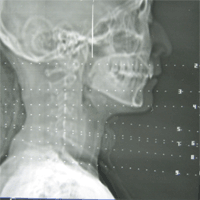

درمان موفقیت‌آمیز سرطان تارهای صوتی با یک روش لیزری جدید

متخصصان در آمریکا موفق شدند؛ با نوعی درمان جدید لیزر، سرطان تارهای صوتی را معالجه کنند.

به گزارش ایسنا، در این روش نوعی درمان ابداعی با لیزر برای مراحل اولیه‌ی سرطان تارهای صوتی که در بیمارستان عمومی «ماساچوست» انجام گرفت، به بازگشت موفقیت‌آمیز صدای بیماران بدون نیاز به پرتودرمانی یا روش قدیمی جراحی منجر شد.

لازم به ذکر است که در روش‌ قدیمی جراحی، خطر وارد شدن آسیب دائمی به تارهای صوتی بیمار وجود دارد.

این گزینه‌ی جدید درمانی تاکنون بر روی بیش از 25 بیمار انجام گرفته که امیدوار کننده و رضایت بخش بوده است.

آمارها نشان می‌دهد که تنها در کشور آمریکا در هر سال حدود چندین هزار نفر به این سرطان مبتلا می‌شوند.